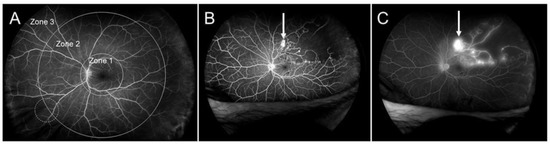

3.4. Retinal Nonperfusion

- Yasuda, Y.; Hirano, Y.; Esaki, Y.; Tomiyasu, T.; Suzuki, N.; Yasukawa, T.; Yoshida, M.; Ogura, Y. Peripheral microvascular abnormalities detected by wide-field fluorescein angiography in eyes with branch retinal vein occlusion. Ophthalmic Res. 2019, 61, 107–114. [Google Scholar] [CrossRef] [PubMed]